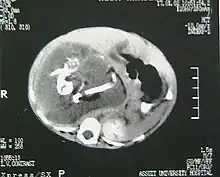

Ocurre en 1 de 1 000 000 nacimientos,[1][2] y se define como una masa fetiforme totalmente encerrada dentro del cuerpo del autósito o hermano desarrollado. Al extraerse, está envuelto en lo que parece un huevo de gallina, pero mucho más grande y extremadamente duro. El parásito, cuando es extraído y expuesto, tiene un color blanco. Una vez que se extrae, muere, ya que es un tejido totalmente dependiente de su hospedador. Al igual que en los gemelos parásitos, corazón y cerebro están ausentes o son muy rudimentarios. Puede estar más o menos organizado, con características muy variables, desde apenas una bola de tejidos hasta contener restos de pelo, hueso, manos con dedos y uñas y hasta piernas. La extirpación quirúrgica no presenta el menor problema dado que no pasan de ser tumores que pueden llegar a ser un potencial riesgo para su hospedador, debido a que se alimenta de este, representando para el hospedador una carga semiviva sin función en el organismo, y pueden llegar a malignizar.[3]